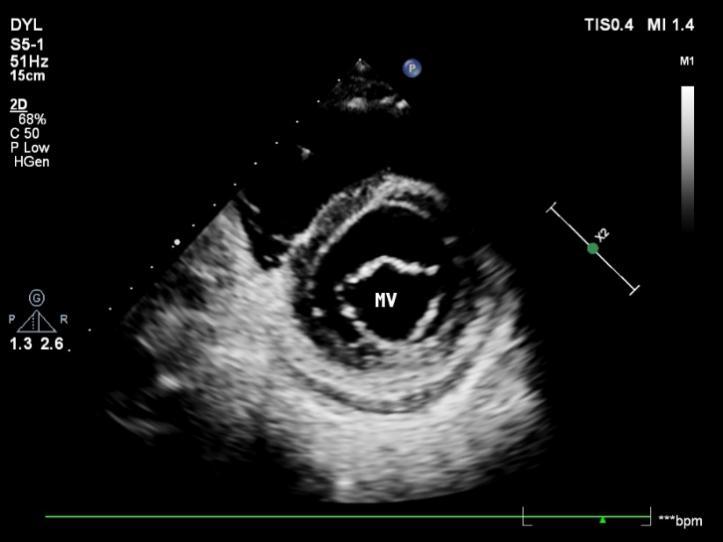

1.2.2二尖瓣水平

胸骨旁左室短轴切面二尖瓣水平二维超声胸骨旁左室短轴切面二尖瓣水平二维超声